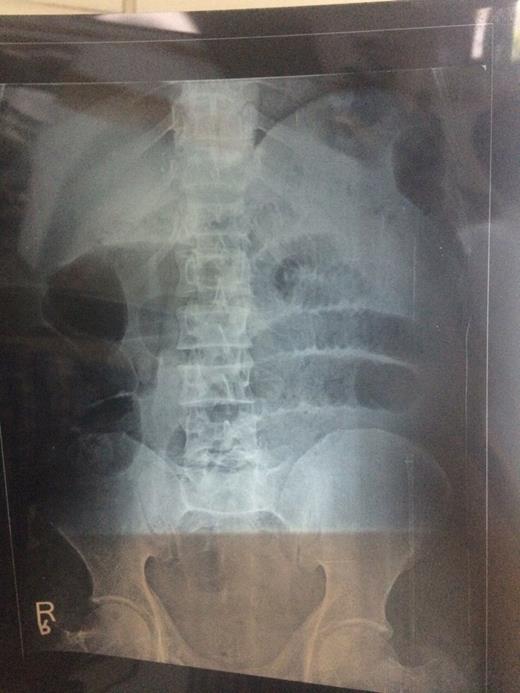

A 51-year-old male was brought in our casuality in shock with history of abdomen pain and non-passage of flatus and stools for 24 h. His blood pressure was 78/56 mmHg and pulse rate was 112 min−1. Abdomen was distended and tender. He was resuscitated, and X-ray of abdomen revealed multiple dilated gut loops as depicted in Fig. 1. Per rectal examination revealed soft faecal matter. Ultrasonography showed multiple dilated gut loops with minimal intergut fluid. CT was not available. Urgent exploratory laparotomy was done. Ileum was wrapped around sigmoid colon making two complete turns with gangrene of sigmoid colon and ileum as depicted in Fig. 2. Clamps applied on large gut and sigmoid colon removed followed by ileum, and end jejunostomy was done in view of haemodynamic unstability of the patient along with descending sigmoid colon anastomosis. The patient expired after 2 weeks despite exhaustive efforts due to complications of short bowl syndrome.

The ISK is rare but life-threatening type of closed-loop intestinal obstruction. The exact mechanism of ISK is still speculative. A long small bowel mesentery, long sigmoid mesocolon on a narrow pedicle and ingestion of high bulk diet after fasting are predisposing factors [1, 6]. The ileal loops can twist around sigmoid colon in clockwise (60.9–63.2%) or anticlockwise direction (36.8–39.1%). The knot is 360° in 52.9%, two 360° turns in 19.1% and three 360° turns in 5.9% cases. ISK is seen predominantly in males (80.2%), with a mean age of 40 years (4–90 years). ISK has been classified into four types as described in Table 2. In the present case, we have Type IA knot (most common variety) with two 360° turns of ileum over sigmoid colon. Atamanalp et al. in 2008 described a new classification of ISK based on age, shock, associated chronic illness and shock as summarized in Table 3. ISK is a known entity for its rapid progression to gangrene. Pain abdomen (100%), abdomen distension (94–100%), nausea and vomiting (87–100%) and shock (0–60%) are usually present at admission [1, 2, 9]. X-ray abdomen reveals a large gas-filled loop of sigmoid colon in the right mid and lower abdomen. Ultrasonography shows dilated gas-filled intestinal loops with free fluid. CT of abdomen can help to clinch the diagnosis in preoperative stage [1, 2]. It can markedly reveal a dilated loop of sigmoid colon with loss of haustration and non-enhancing thinned out wall. The characteristic whirl sign (twisted mesentery and bowel) is another feature. Convergence of superior mesenteric vein towards knot and medial pointing of caecum are other suggestive findings. Despite availability of various modern diagnostic tools in the present era, only 0–28% cases could be diagnosed preoperatively [3, 10].